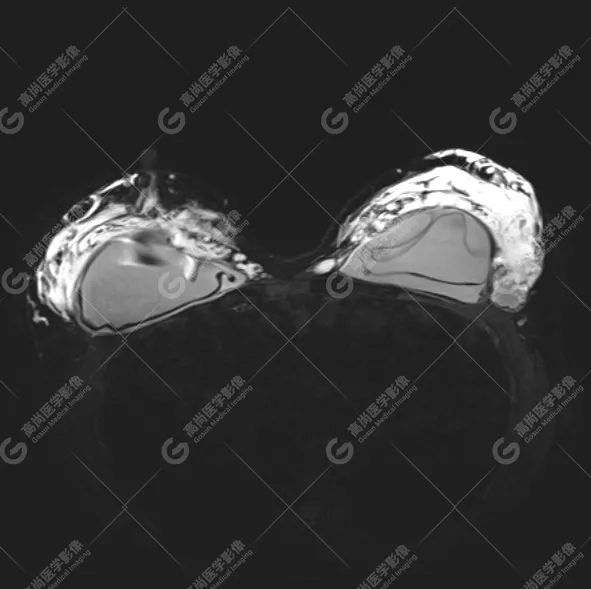

病例 1:乳腺假体植入术后 3 月余

双侧假体包膜光滑完整,内容物信号均匀。